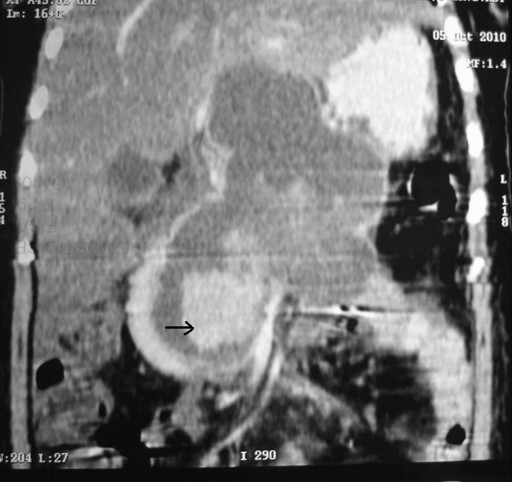

A 26-year-old female presented with a 2-month history of abdominal pain. She was admitted to our institution 7 days after the onset of the pain. She was diagnosed as having gallstone-induced severe acute pancreatitis with a large peripancreatic fluid collection. She was discharged on the 17th day after admission; a cholecystectomy and follow-up for the fluid collection were recommended. Three weeks after discharge, she developed sudden onset of severe abdominal pain with passage of black tarry stool. Hemodynamic stability was maintained. She was re-admitted to our institution. At admission, her pulse was 96 min-1 and her blood pressure was 100/70 mmHg. A lump was palpable in the epigastric region which was non-pulsatile. Hemoglobin was 7.8 g/dL (reference range: 11.5-15.5 g/dL). Upper gastrointestinal endoscopy showed blood in the stomach and duodenum with erosions in the body and antrum of the stomach. She was treated with proton pump inhibitors and blood transfusions. Four days after re-admission, she experienced one episode of hematemesis, and an upper gastrointestinal endoscopy showed blood trickling from the papilla; it was diagnosed as a case of hemosuccus pancreaticus. Contrast-enhanced computed tomography of the abdomen showed a large pseudocyst with extravasation of contrast within the cyst (Figures 2 and 3). The source of bleeding was not identified. Angiography identified a pseudoaneurysm of the gastroduodenal artery. Angioembolization failed due to technical reasons (partial embolization due to a rich collateral supply) and the patient had to undergo emergency surgery. We found that the pseudocyst was full of blood clots and there was a blister-like area in the wall of the cyst (Figure 4). After removal of the clots and slight pressure on the blister-like area, arterial bleeding was seen which was controlled with 4-0-polypropylene sutures. The pseudocyst was drained into the stomach. The patient had an uneventful postoperative course and was well at a 7-month follow-up.

Figure 3. CECT abdomen (coronal) showing a large pseudocyst with extravasation of contrast within it (black arrow) (Case #2). |